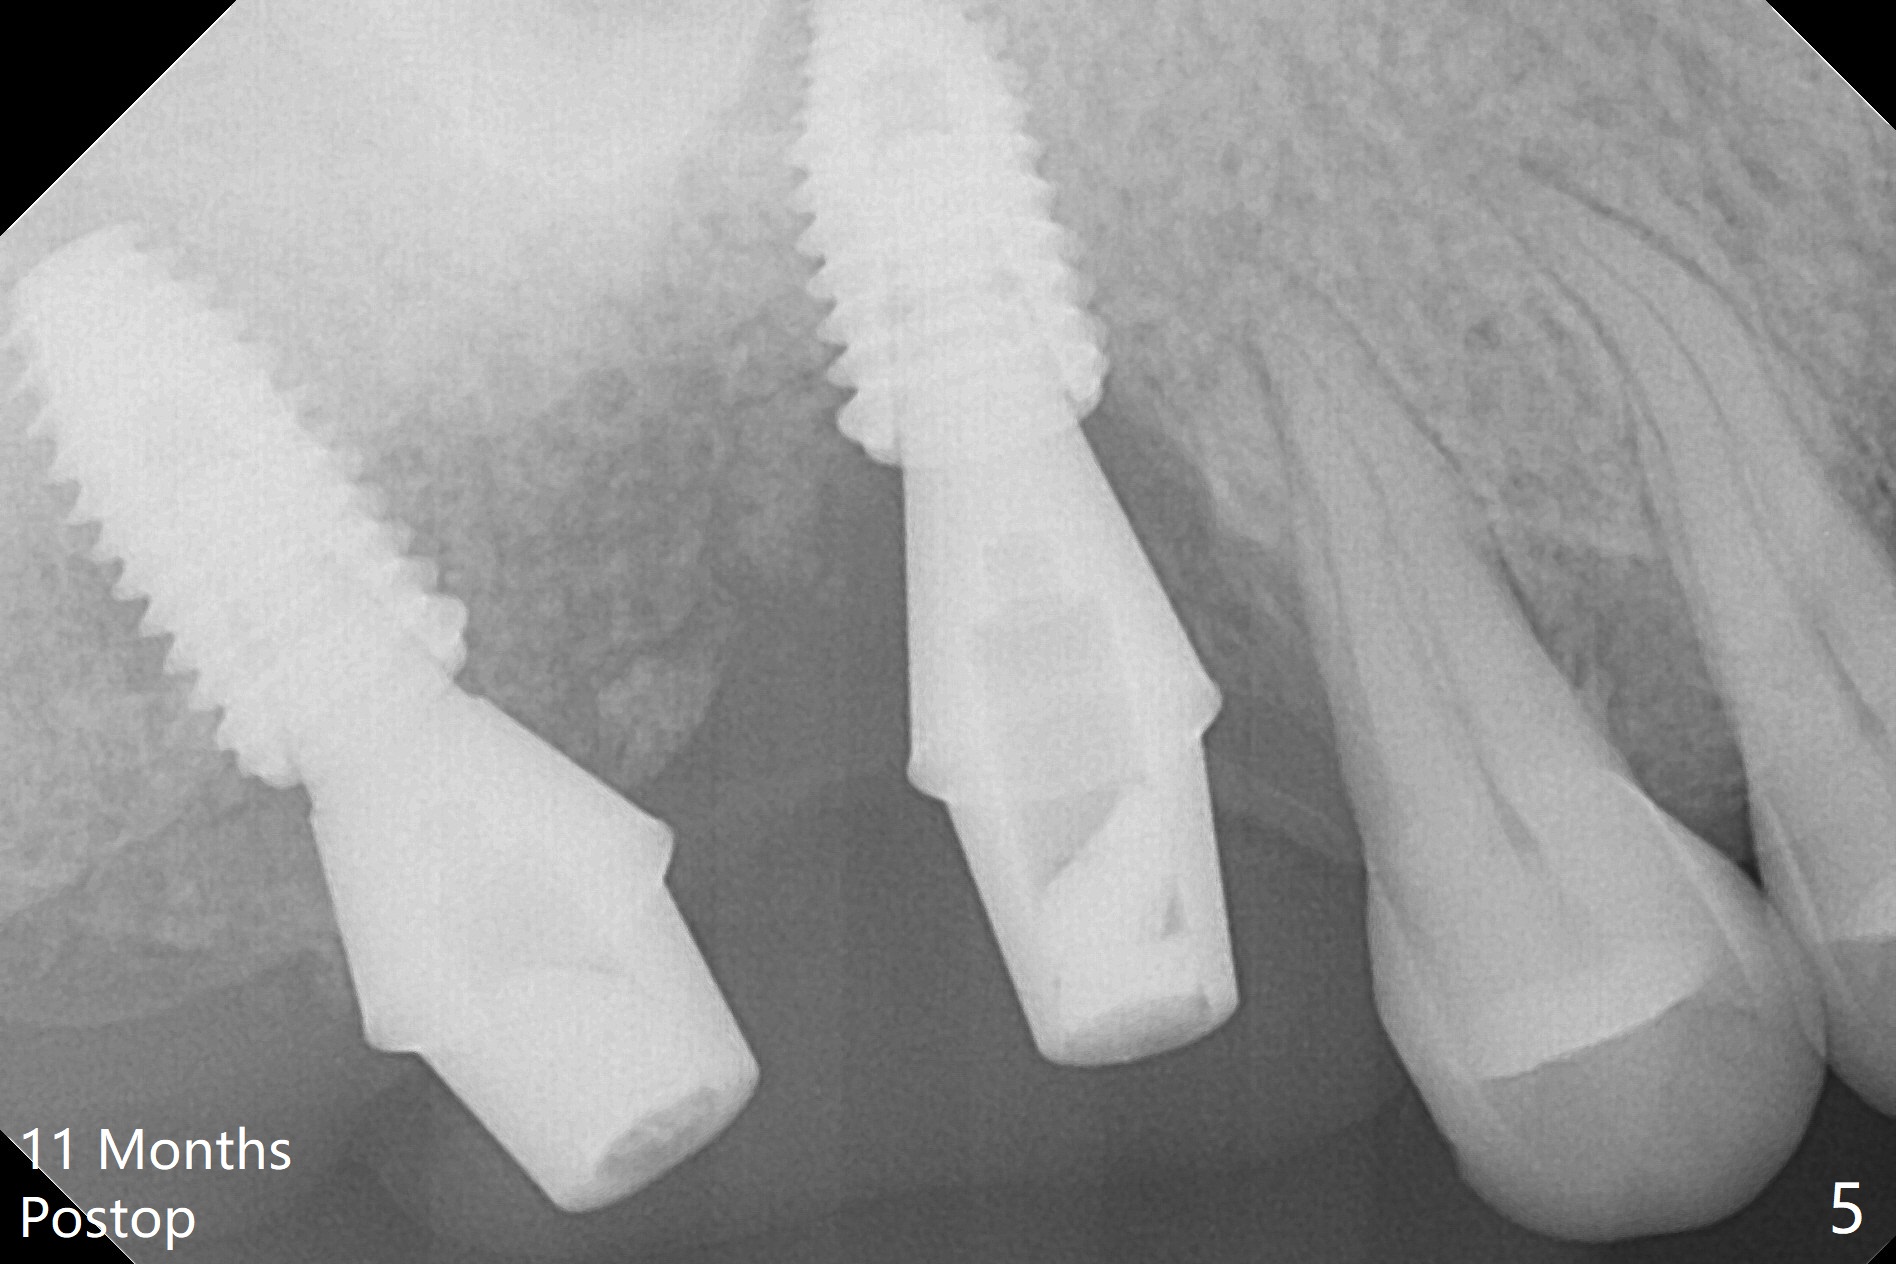

After use of 2.2 mm IS drill, DIO parallel pins are unstable at #2 and 3, partially due to shallow osteotomy. PA is not taken with parallel pins. When dummy implants are placed, the axis at #3 is noted; but instead of moving the apical end of the osteotomy distal (Fig.1 red line), the coronal end is moved mesial. By the time definitive implants and abutments are placed, the axis of #3 is parallel to that of #4, but close to each other (Fig.2,3). Orthogonal panoramic X-ray shows that they are critically close (Fig.4). If PA were taken with parallel pins after initial osteotomy, correction would be easy. The patient is doing fine postop without pain or nasal hemorrhage. There is no thread exposure 11 months postop (Fig.5). The abutment screw at #3 is retightened 7.5 months post cementation (Fig.6 (poor crown/implant ratio)).